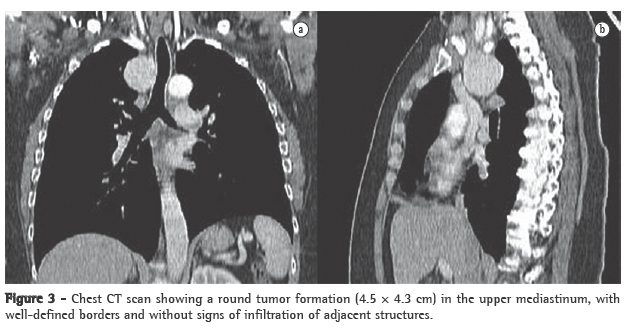

Another chest X-ray, performed on postadmission day 8, showed that the opacity described above persisted. Subsequently, a CT scan of the chest, performed to clarify this issue, revealed a solid formation in the anterior mediastinum. The formation measured 10 cm in its largest diameter and maintained cleavage planes with the heart and the lung, as well as insinuating itself between the lung lobes and compressing them. In addition, a magnetic resonance imaging scan was performed to determine the true extent of the lesion, especially in terms of the cleavage plane with the mediastinal structures (Figure 2), and the findings confirmed those of the CT images.

The patient was then referred for surgery, which allowed the excision of an anterior mediastinal mass (measuring 12 × 9 cm and weighing 400 g), well delineated by a capsule, and whose histology corresponded to ectopic thyroid tissue, the morphology overlapping with that of nodular thyroid hyperplasia but differing from it by presenting microfollicles containing colloid as well as an adjacent inflammatory reaction (Figure 2).